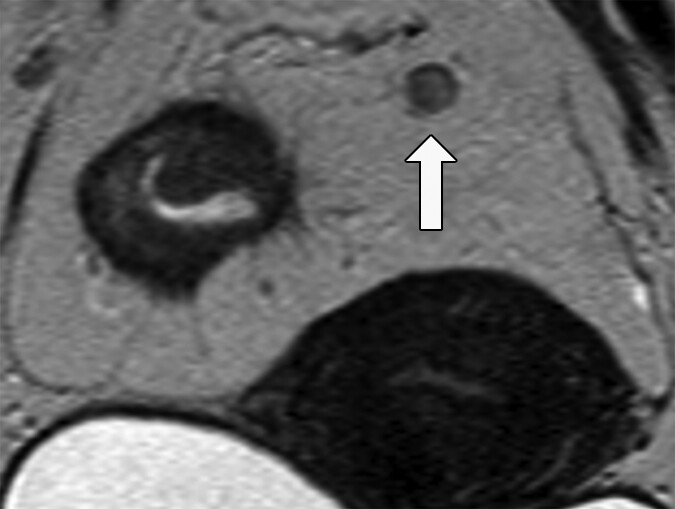

Fig. 2—Morphologic features of metastatic mesorectal nodes on MRI

and potential pitfalls in assessment. 58-year-old woman with rectal

adenocarcinoma. Oblique axial T2-weighted MRI (left) shows apparently

spiculated node (arrow). Graininess of image is related to poor signal-tonoise

ratio (SNR). Coronal T2-weighted MRI (right) shows that same node is

homogeneously T2 hyperintense with dark capsule (arrow), which is typical

of reactive mesorectal node. This image has superior SNR. Suboptimal images

can lead to erroneous assessment of nodal morphologic features. This

patient proceeded directly to surgery. Total of 38 lymph nodes (0.3–1.3 cm)

were harvested. Eleven of larger lymph nodes were serially sectioned before

submission for histologic processing. Final pathology revealed T3N0 disease.